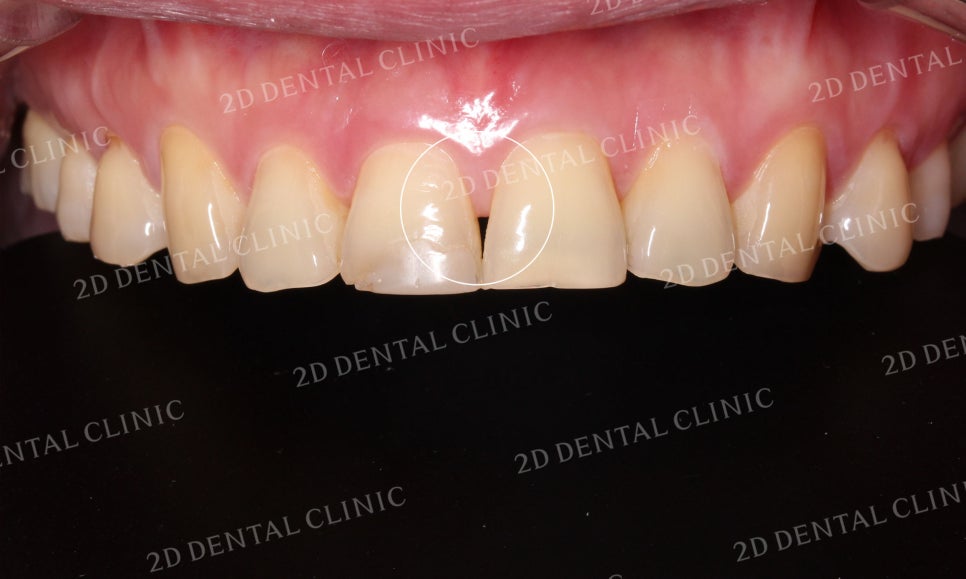

상악 전치부의 사진입니다.

환자분께서는 상악에 총 6개의 블링스를

부착하셨는데요,

블링스 시술 전 중절치 쪽의

잇몸이 후퇴하여 뿌리가 드러나

블랙트라이앵글이 생겼습니다.

그러나 전치부 6개의 블링스 시술 후

블랙트라이앵글은 물론

누렇게 착색되었던 치아의 색상도

밝은 상아색으로 돌아온 모습입니다!